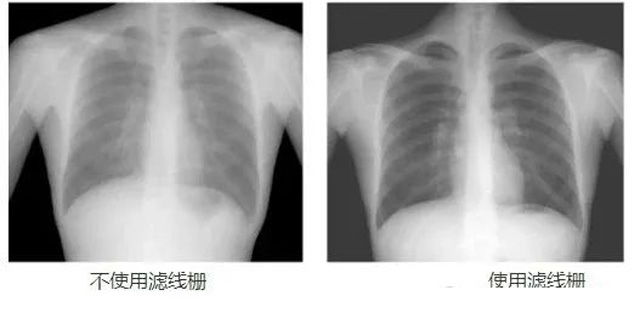

DR影像X射线在医学检查成像有着广泛的使用。但是它的散射线影响成像质量问题。滤线栅的发明使用很好的解决了这个问题,构造简单铅条粗,密度和栅比规格单一,能减散射线但吸收较多原发射线。伴随这医疗影像设备技术的发展,这个滤线栅的工艺制造技术有改进,铅条变薄,栅密度和栅比有更多的选择。特别是材料方面有新组合,填充物也依不同成像要求优化。特别是移动DR这类型的DR设备的出现,滤线栅也设计成立方便拆卸形的,方便使用。被照体情况决定是否使用,更好平衡成像质量与射线剂量。

放置方面:置于人体与片盒间,聚焦面朝向X线入射方向,X线焦点放铅条会聚线上,不能反置,X线中心对准滤线栅中心,左右偏移不超3cm,倾斜X线管要与铅条排列方向平行。摄影时焦距改变不超焦距的25%;活动式滤线器运动时间至少长于曝光时间的1/5;因吸收原发射线要适当增加曝光条件;四肢薄位置一般不用滤线栅;不同千伏对应不同栅比;立位胸片架、乳腺DR摄影等有各自特定滤线栅要求。